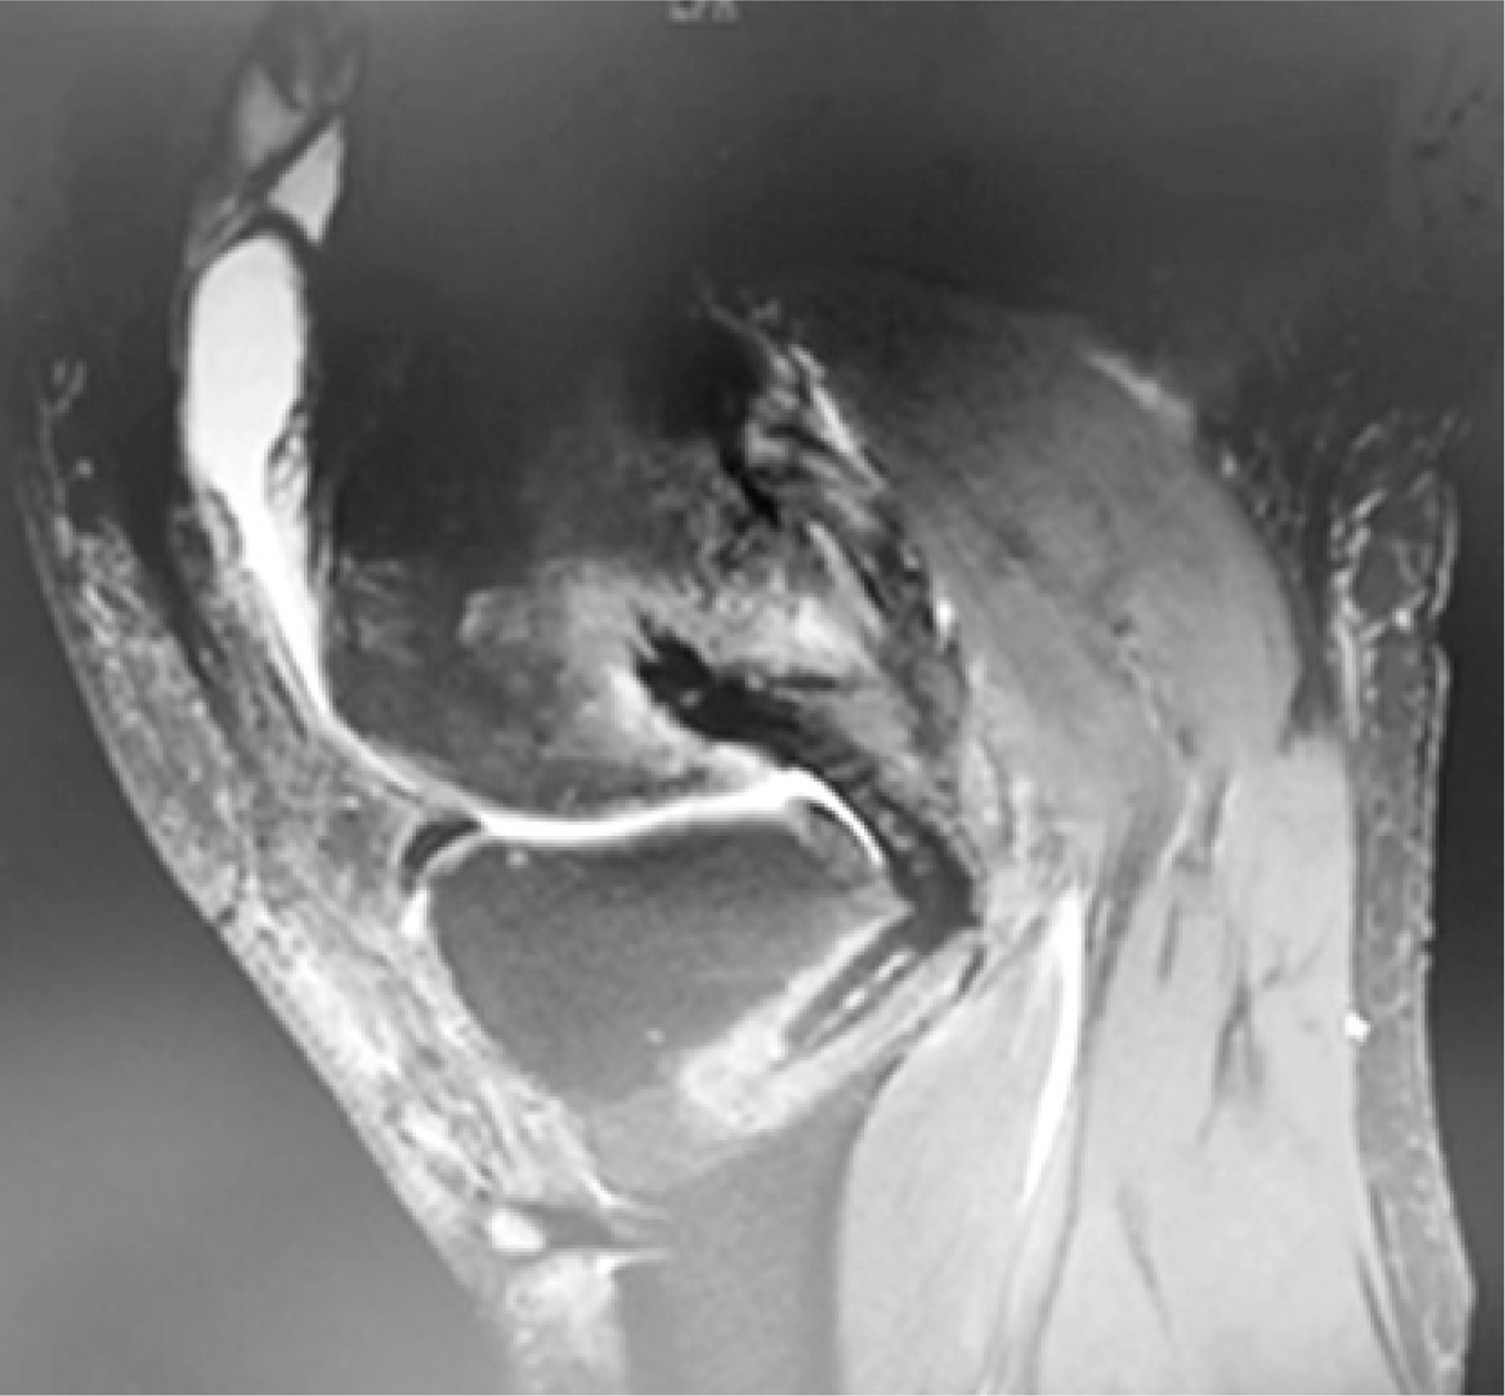

The study group underwent autologous hamstring tendon single-bundle reconstruction combined with braided thread treatment. It adopts double Endo-Button technology and uses Ethicon thread to knit with a flat knot (Figure 1). The technique is as follows: Braid to the desired length, wrap and suture the tendon around the braided wire (the total diameter of the graft is 9 mm) (Figure 2). MRI taken intraoperatively as well as pre- and postoperatively are shown in Figures 3–5.